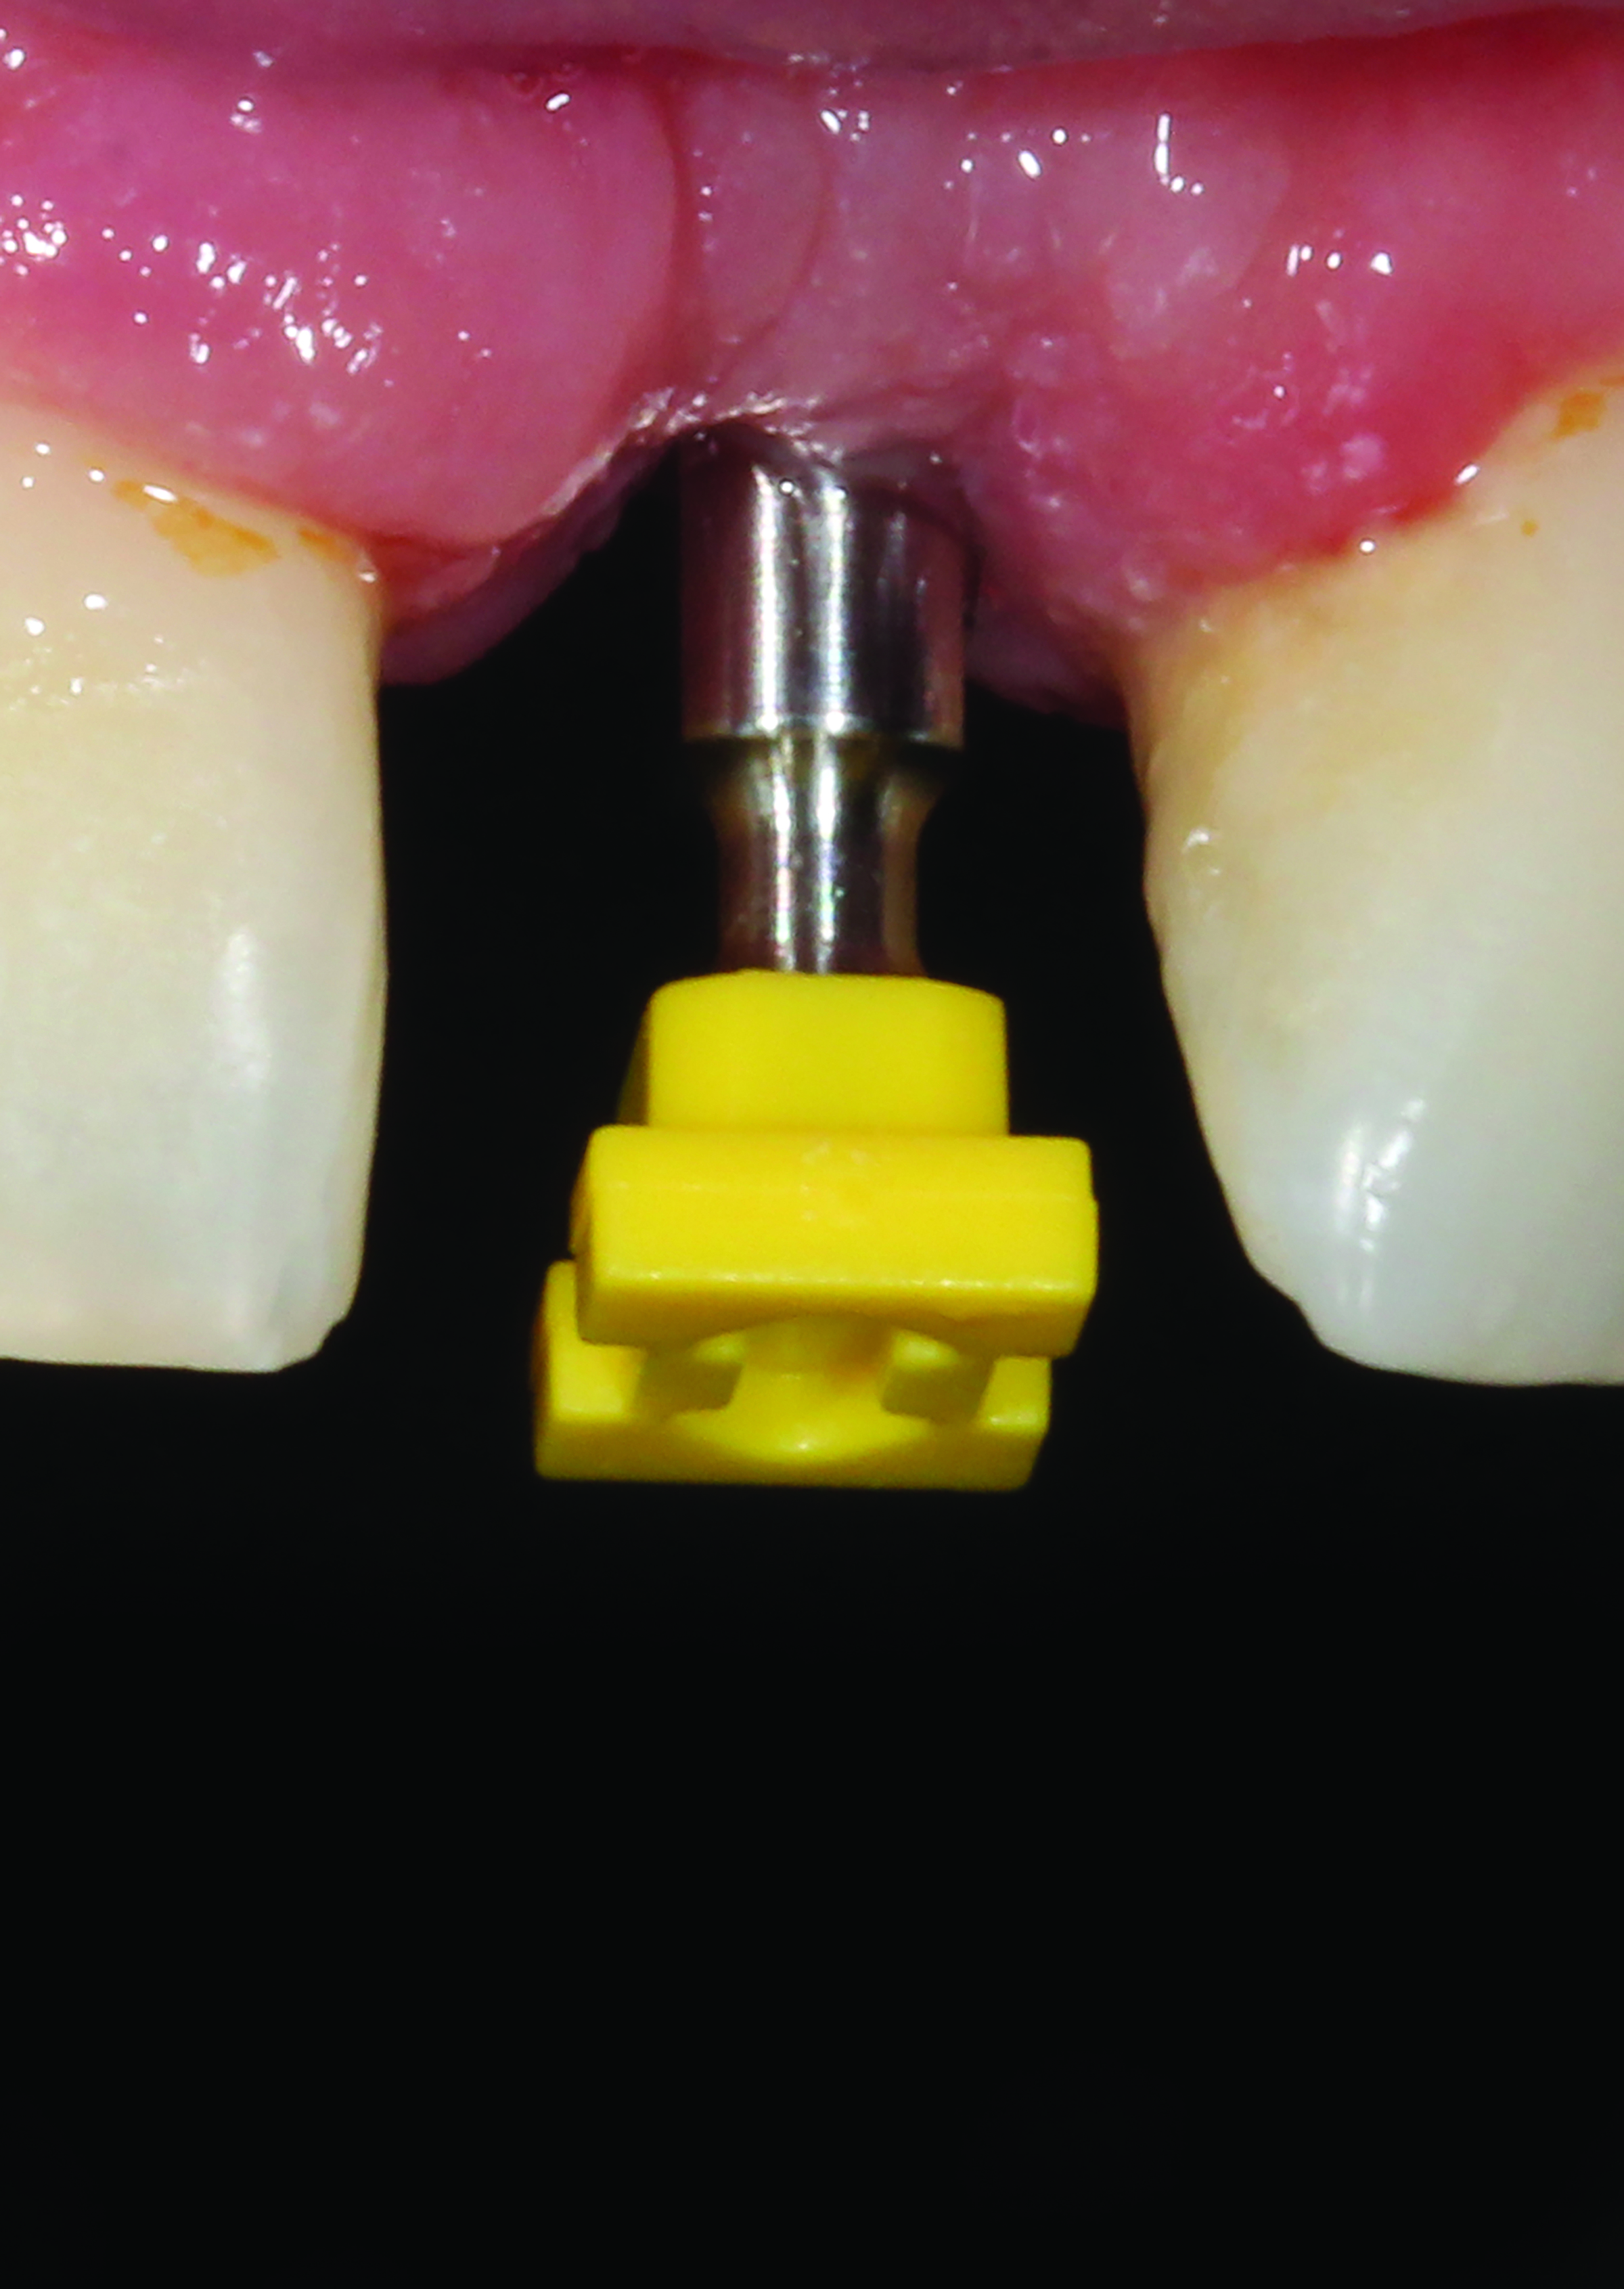

Fig 7. A closed-tray impression coping before the impression is made. <br>

Figure 7